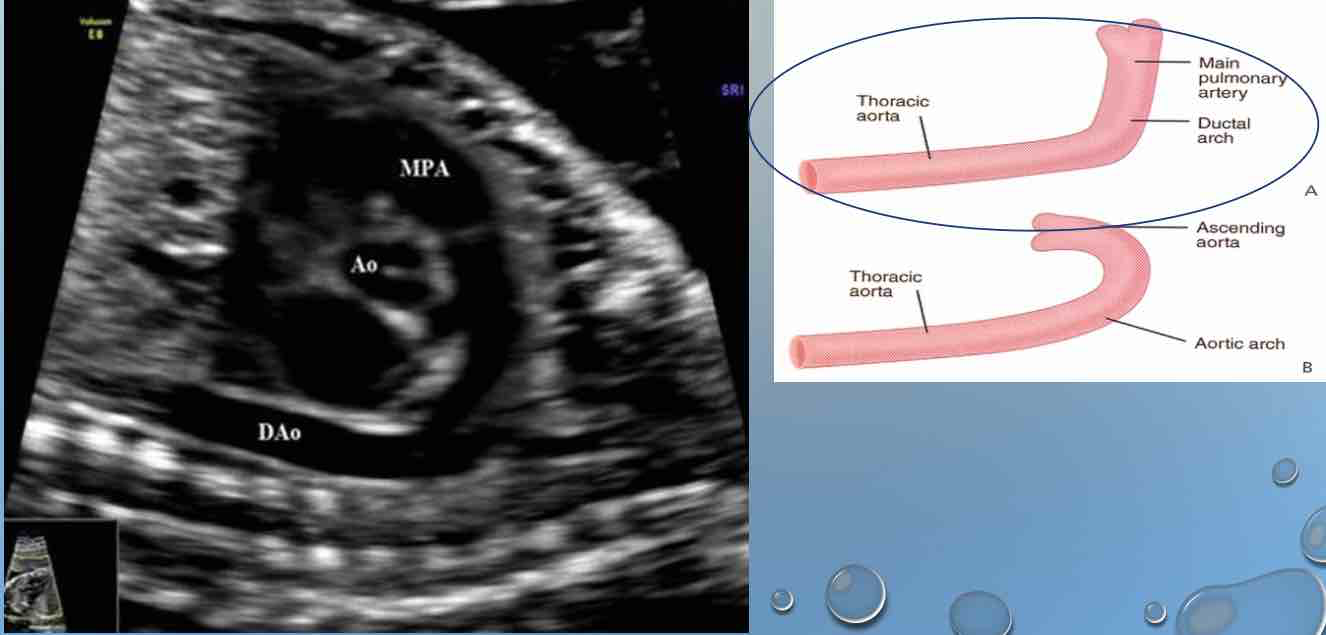

Q

Image 4:

LVOT (AORTA)

A

THE AORTA ARISES FROM THE POSTERIOR ASPECT OF THE LEFT VENTRICLE

THE AORTA (AO) AND PULMONARY ARTERY (PA) CROSS OVER EACH

OTHER AS THEY EXIT THEIR RESPECTIVE VENTRICLES OF THE HEART

FIVE CHAMBER VIEW OF THE HEART

THE FIVE CHAMBER VIEW IS OBTAINED BY ANGLING THE TRANSDUCER

CEPHALAD AND ANTERIOR FROM THE FOUR CHAMBER VIEW.